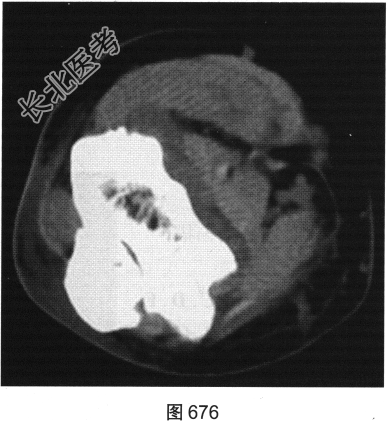

患者女性,62岁,右侧肘关节肿胀、疼痛1年余。肘关节正侧位X线片及CT检查见图673~图676。

- 多项选择题1.对该患者影像征象描述正确的是( )

A、关节腔积液

B、尺骨关节面囊状骨质破坏

C、肘关节面明显骨质增生硬化

D、肘关节软组织肿胀

E、尺骨近段骨膜反应

F、肘关节间隙变窄

G、骨质疏松